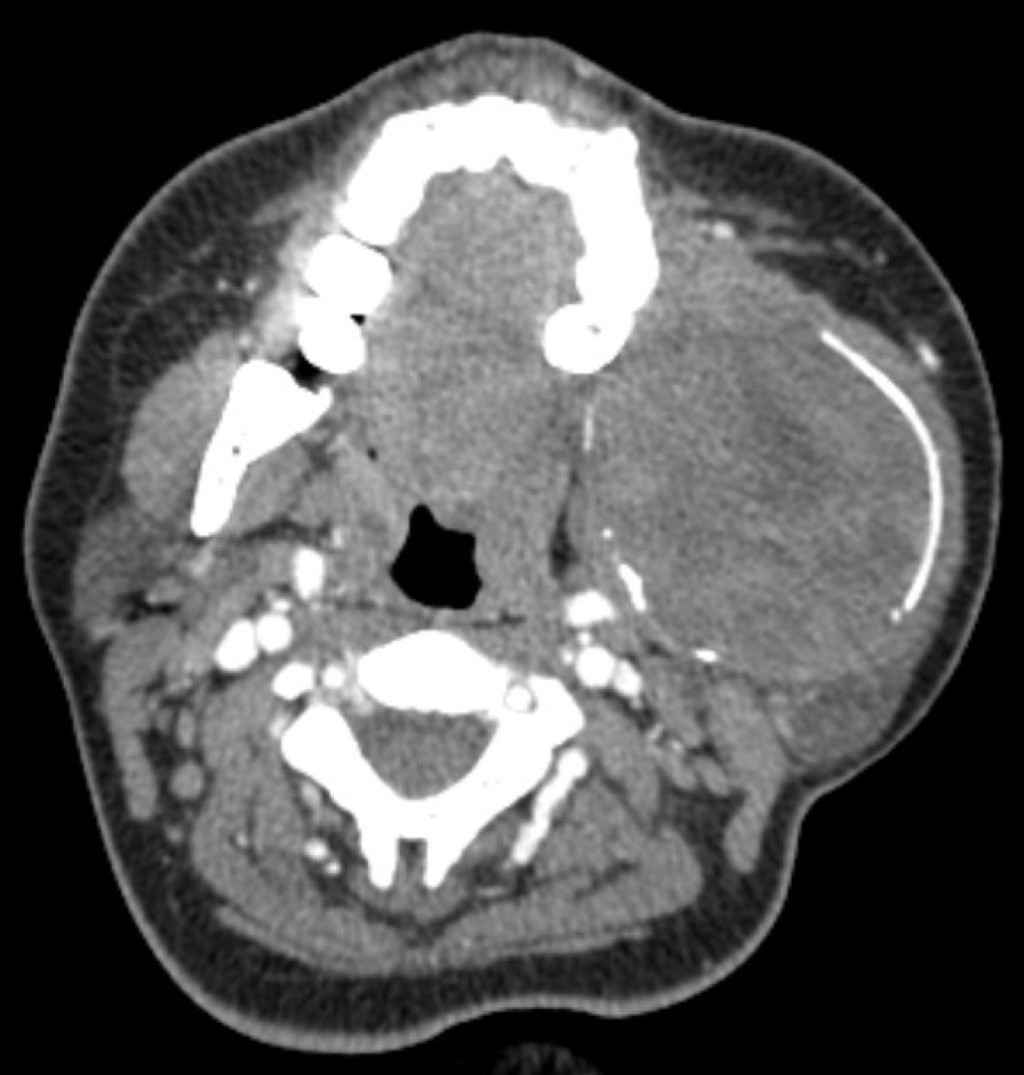

La tomografía contrastada mostró una lesión osteolítica bien delimitada con bordes escleróticos, afectando cóndilo, rama y cuerpo mandibular izquierdo posterior al primer premolar; la lesión medía 56 × 70 × 66 mm, con erosión del maxilar izquierdo y desplazamiento de arteria carótida externa y vena yugular interna (Figuras 2, 3, 4, 5 y 6).

Figura 2

Figura 3

Figura 4

Figura 5

Figura 6